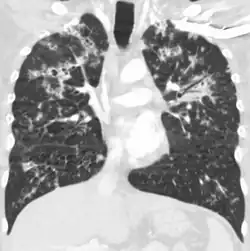

Seu nome se refere a similaridade dos seus focos de infecção com grãos de milho espalhados pelo pulmão em 90% dos exames de raio-X.

A Tuberculose miliar ou tuberculose cutânea aguda disseminada é uma classificação médica internacional para um agravamento da tuberculose por sua ampla difusão dentro do corpo humano gerando pequenas lesões na pele (de 1 a 5mm).[1]